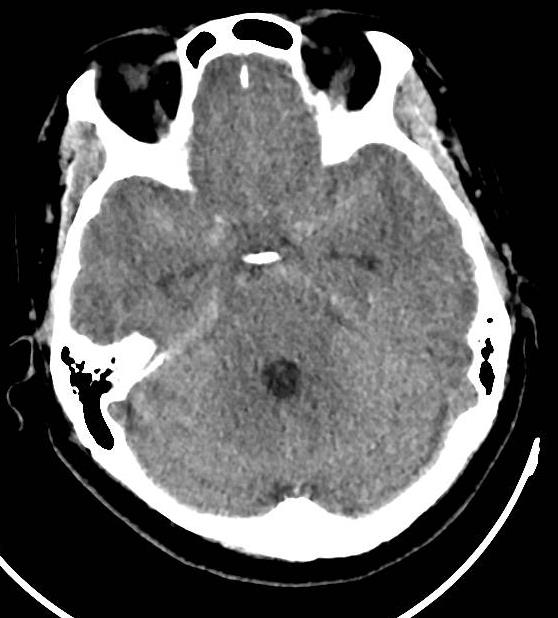

诊疗经过:入院时颅脑CT示蛛网膜下腔出血